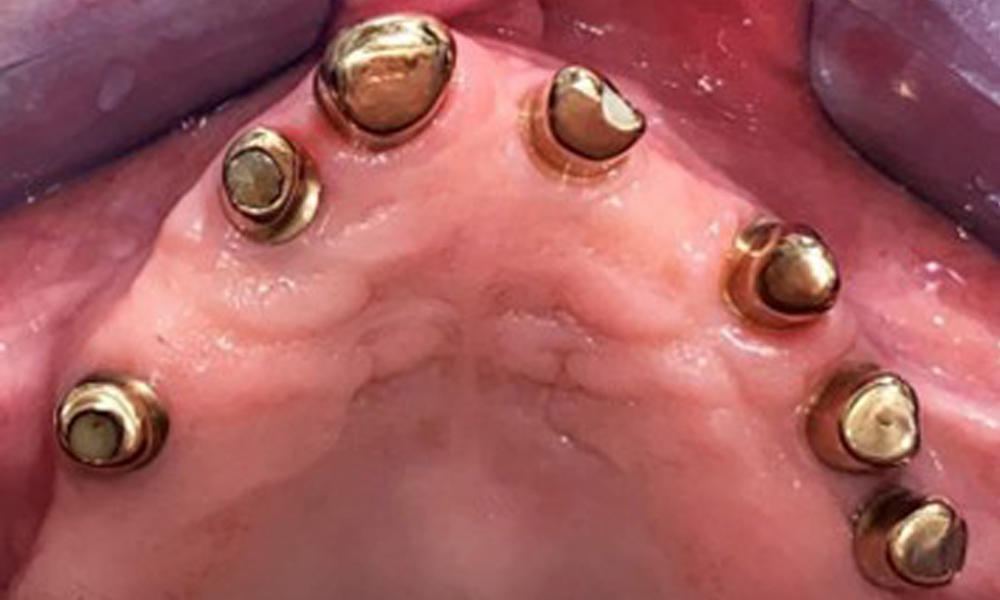

The dental findings are as follows: Combined removable implant and tooth-supported telescopic prostheses on implants 15, 13, 21, 23, 24, 25 and tooth 11 (Fig. 1, Fig. 2, Fig. 3). The patient was fitted with a fixed mandibular denture. Adequate bridges were present over 37 to 34 and 45 to 47 (Fig. 4), the crown margins were intact and there were no active caries. A composite filling with a marginal gap was present on tooth 43. There was mandibular gingival recession, exposing 1 to 3 mm of root surface. This also applies to 11.

Occlusal view: Maxilla with tooth and implant-supported telescopic prostheses.

Fig. 2: Occlusal view: Maxilla with tooth and implant-supported telescopic prostheses